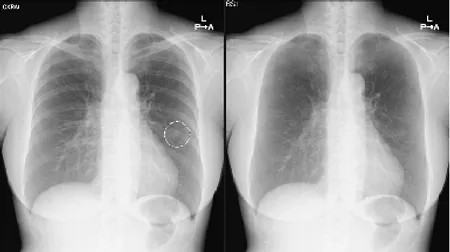

胸部X線画像から肺結節候補域を検出

胸部単純X線画像を自動解析。結節・腫瘤影、浸潤影、気胸が疑われる領域を検出しマーキングします。

胸部X線画像における包括的な読影支援を提供